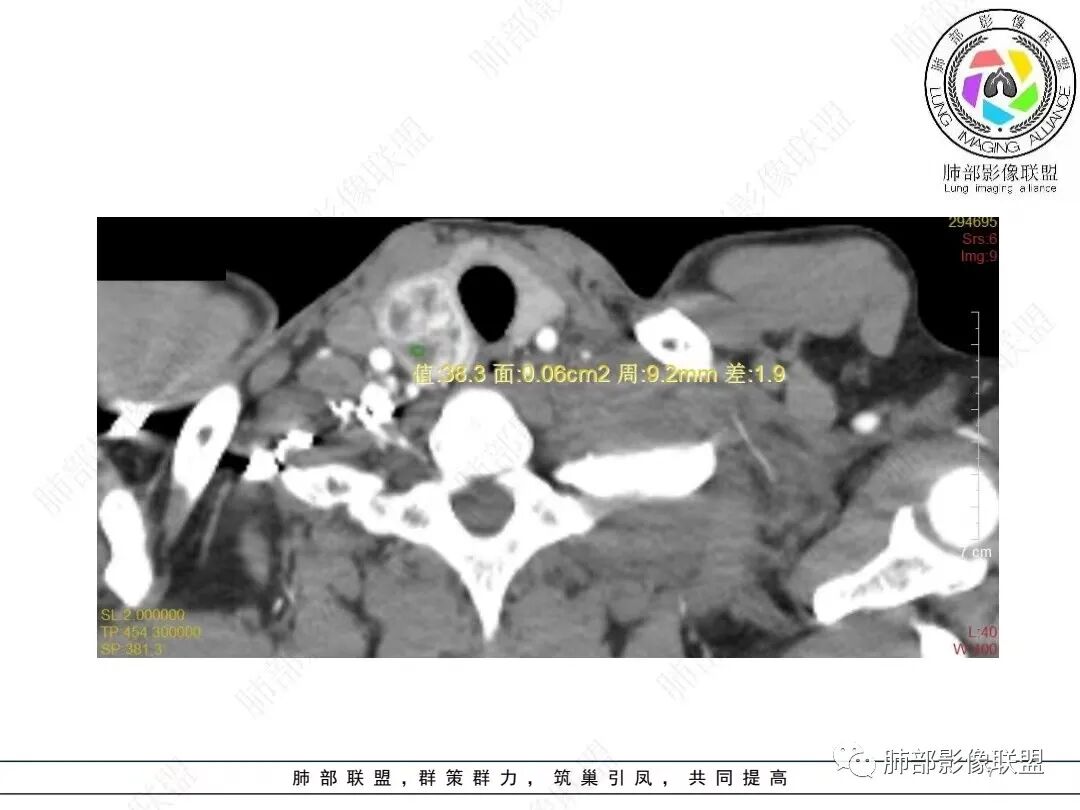

男,52,胸闷、气短、咳嗽1月。长期吸烟,NSE、细胞角蛋白19片段增高。胸部CT:甲状腺右叶结节,增强可见多发低密度区。纵隔、肺门多发淋巴结肿大融合,周围脂肪间隙消失,冰冻纵隔;针孔状食管;两侧胸腔积液伴肺不张,左侧重,胸水清澈。考虑恶性,SCLC?鉴别淋巴瘤、转移瘤等。

1.临床特点:患者,男,52岁,长期吸烟史,胸闷、气促伴刺激性咳嗽一月入院,查体发现前上腹包块。细胞角蛋白19片段、神经元特异性烯醇化酶升高。

甲状腺右叶相对低密度结节影,边界清楚,不均匀分隔样强化,经验上分析与胸部病灶缺乏关联性。